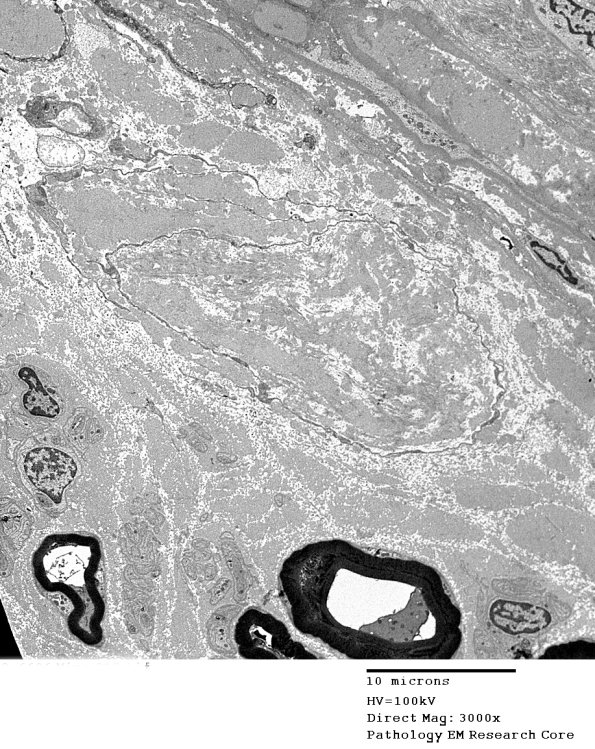

A second smaller RB is shown at higher magnifications in the following images. (electron micrograph)